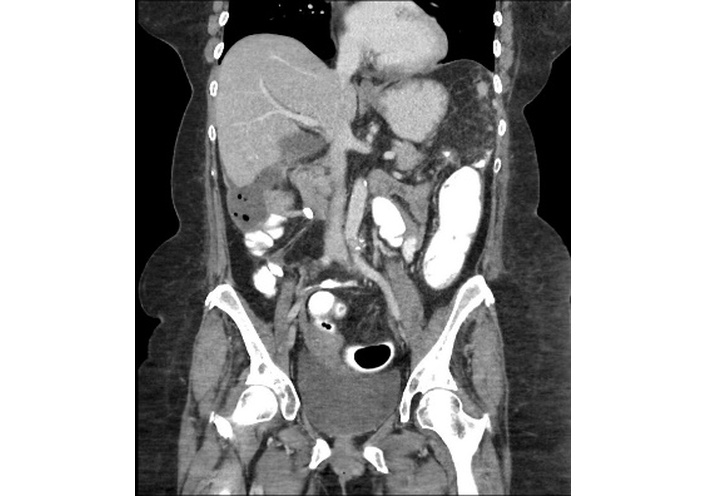

Five days post-discharge, the patient returned to the general surgery clinic with purulent drainage from a right pelvic Jackson-Pratt drain and right flank pain and was sent directly to her local emergency department for further evaluation. Vitals revealed (temperature 37.3°C, heart rate 115 bpm, respiratory rate 18 breaths per minute, blood pressure 126/76 mmHg, oxygen saturation 98% on room air). Laboratory results included WBC 18.9 × 103/µL, HGB 9.4 g/dL, PLT 490 × 103/µL, ALB 3.0 g/dL, and CRP 13.98 mg/dL. A contrast-enhanced (IV, PO, and rectal) abdominal CT showed post-surgical changes but no small bowel obstruction or contrast extravasation. A 4.0 cm × 7.4 cm × 7.2 cm rim-enhancing fluid collection with multiple air foci was identified in the right hemiabdomen (Figure 5). Physical examination, once admitted to the general surgery service, revealed greenish discoloration on the surgical dressing. Upon removal, a wound gap with fascial separation was identified, along with fecal leakage into the wound from a separated stoma appliance. Exploratory laparotomy confirmed mid-abdominal fascial dehiscence and a peri-hepatic abscess. The abscess was evacuated, the right Jackson-Pratt drain was repositioned, and a new left upper quadrant drain was placed. Wound cultures were polymicrobial, including 1+ Candida albicans. The treating teams initiated IV ciprofloxacin, IV metronidazole, and IV fluconazole, while low-dose PO prednisone 20 mg was continued due to concerns for secondary adrenal insufficiency from the prior hospitalization. By hospital day 3 of readmission, she had remained afebrile and without leukocytosis for 24 hours. She was discharged on PO ciprofloxacin, PO metronidazole, and PO fluconazole to complete a 3-week course.

Coronal contrast-enhanced CT of the abdomen demonstrating a 4.0 cm × 7.4 cm × 7.2 cm rim-enhancing fluid collection with multiple air foci located in the right hemiabdomen, consistent with an intra-abdominal abscess.